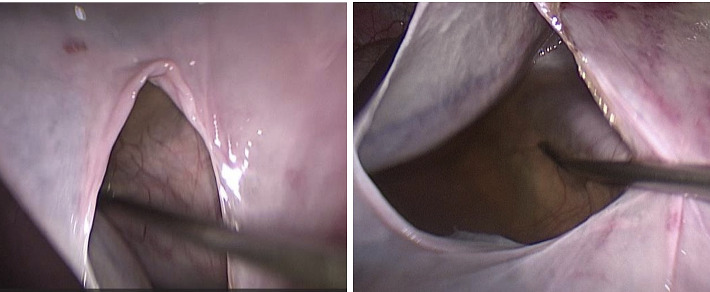

Simple renal cysts are the most common cystic abnormalities of the kidney, typically observed in older individuals and often asymptomatic, requiring no treatment. These cysts are usually detected incidentally during imaging for unrelated conditions. Giant renal cysts, defined as those exceeding 15 cm in diameter and containing over 1500 mL of serous fluid, are exceptionally rare. We report a case of a 34-year-old male presenting with a rapidly growing giant renal cyst (40 × 28 cm) in the left kidney, resulting in malnutrition and significant weight loss. The patient underwent successful laparoscopic transperitoneal cyst excision. At the 1-year follow-up, the patient was asymptomatic, with no evidence of residual cyst recurrence.

单纯性肾囊肿是最常见的肾脏囊性异常,通常在老年人中观察到,通常无症状,无需治疗。这些囊肿通常是在成像时偶然发现的。巨大肾囊肿,定义为直径超过15cm,含有超过1500ml浆液的囊肿,极为罕见。我们报告一例34岁男性左肾出现快速生长的巨大肾囊肿(40 × 28 cm),导致营养不良和体重明显下降。患者接受了成功的腹腔镜经腹腔囊肿切除术。随访1年,患者无症状,无残留囊肿复发迹象。